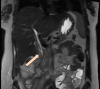

Figure 5. MRCP Promovist

The arrow is pointing at the injured site in the distal CBD MRCP: magnetic resonance cholangiopancreatography; CBD: common bile duct